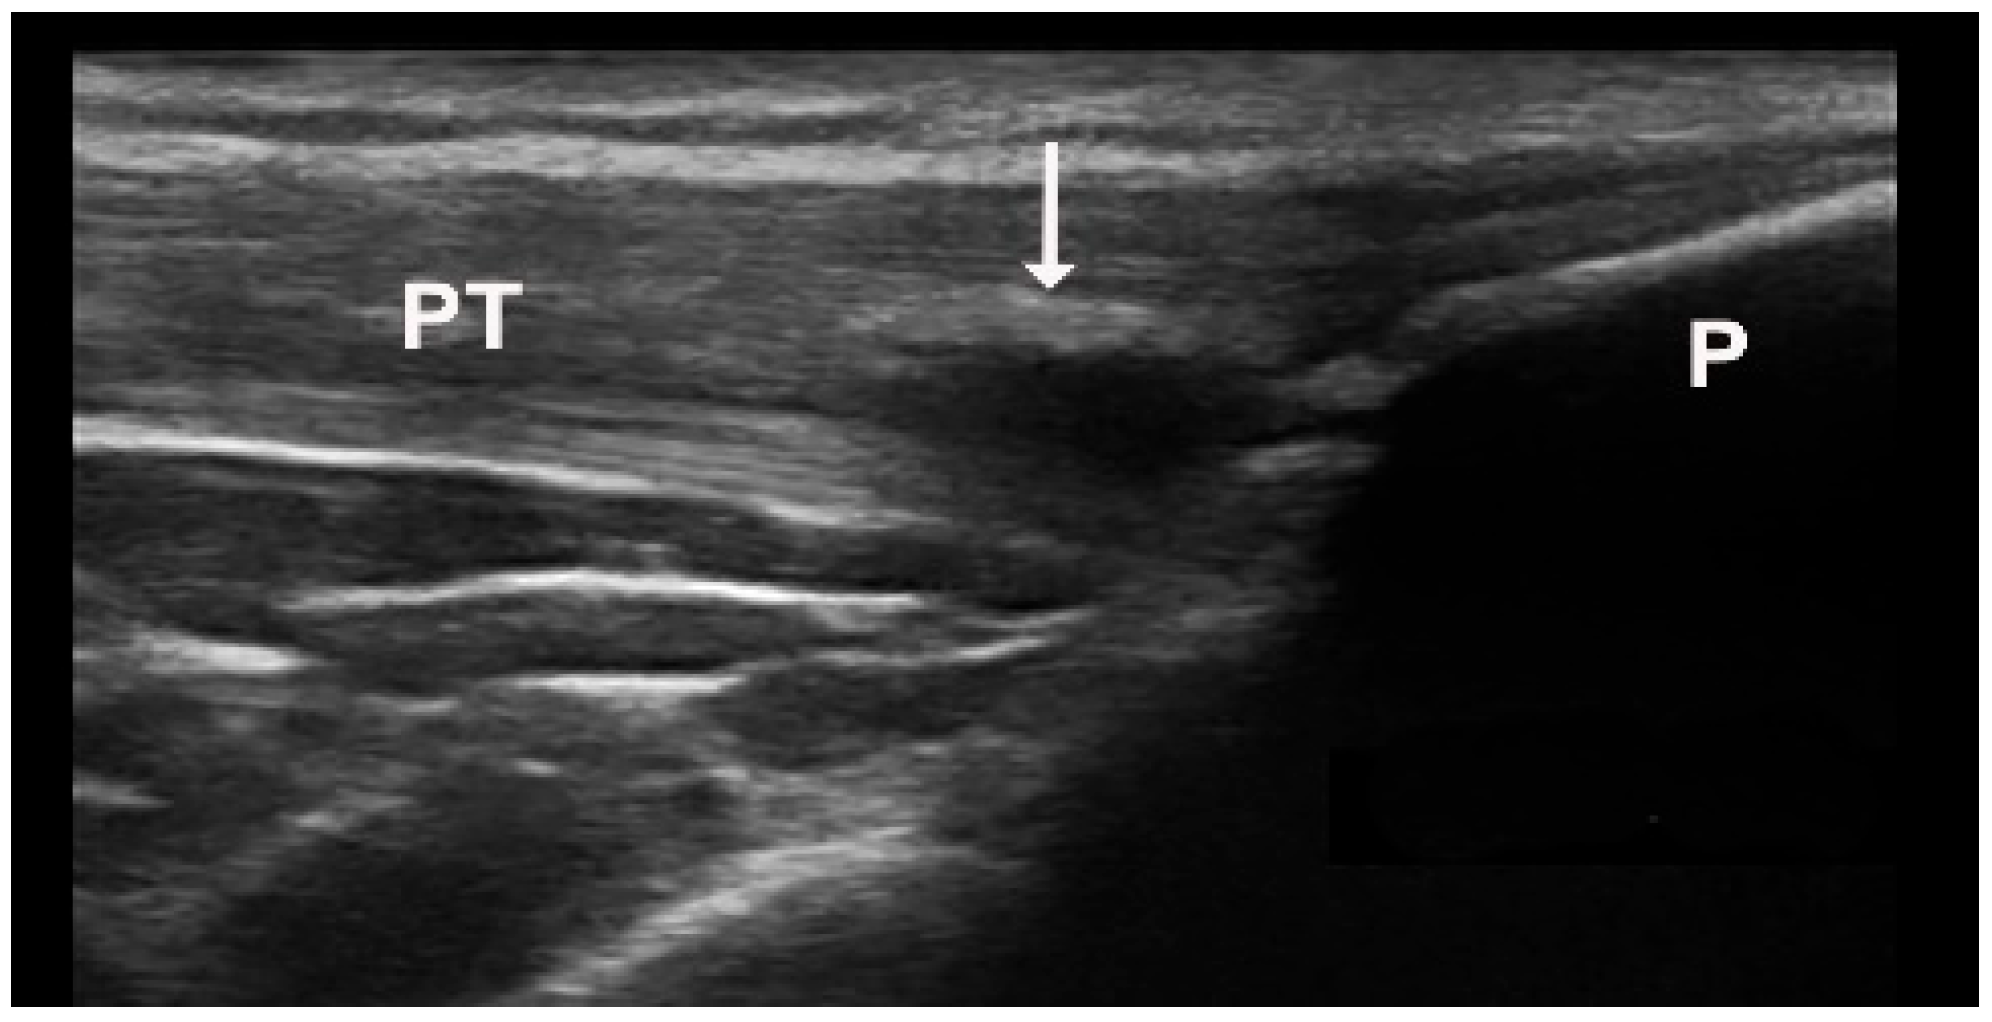

Figure 4.

Intratendinous hard tophus visible in longitudinal view of the distal insertion of the patellar tendon. Notice the posterior shadowing from the tophus. P—patella, PT—patellar tendon, arrow—intratendinous hard tophus.